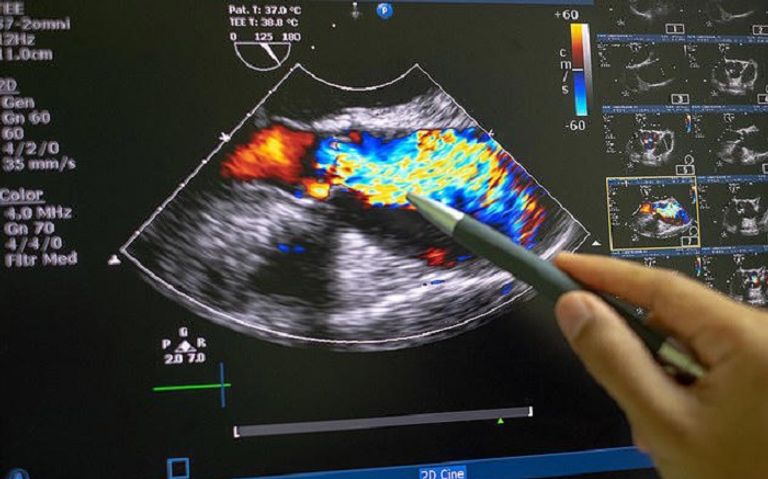

وتُعتبر الصمامات القلبية من العناصر الحيوية التي تنظم تدفق الدم بين الأوعية والقلب، وفي حال تعرض هذه الصمامات للتلف، يمكن أن يؤدي ذلك إلى مضاعفات خطيرة مثل قصور القلب والسكتات الدماغية.

وتعتمد التقنية المبتكرة على ثلاث مراحل رئيسية، كما شرحت الدراسة المنشورة في مجلة "نيتشر كومينيكيشن بيولوجي".